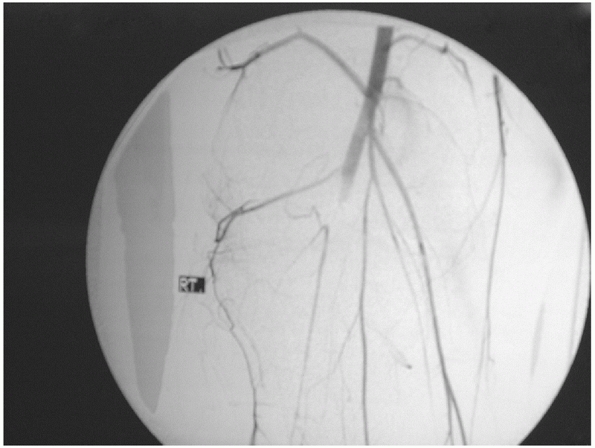

![]() |

|

FIGURE 54-6

An arteriogram demonstrating disruption of the popliteal artery following a knee dislocation. (From Stannard JP, Schenck RC Jr. Knee dislocations and ligamentous injuries. In: Stannard JP, Schmidt AH, Kregor PJ, eds. Surgical Treatment in Orthopaedic Trauma. New York: Thieme, 2007:687-712, with permission.) |